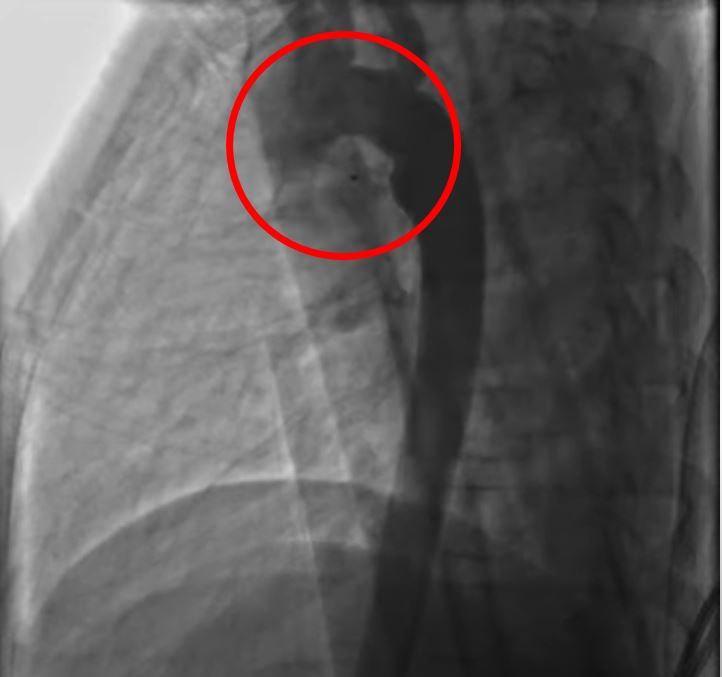

右圖:經心導管治療放置閉鎖器後,血液不再流入肺動脈。

裘品筠醫師提到,大部份的開放性動脈導管,已可用心導管的技術,放置螺旋線圈或關閉器來關閉,很少需要開刀治療。若是用藥反應不佳有症狀的嬰幼兒、嬰兒初期有嚴重的心臟衰竭、不適宜作導管栓塞術的病童需要手術治療外,出生體重少於一千公克的早產兒,則需提早做動脈導管結紮手術,以改善心衰竭及減少壞死性腸炎的發生率。